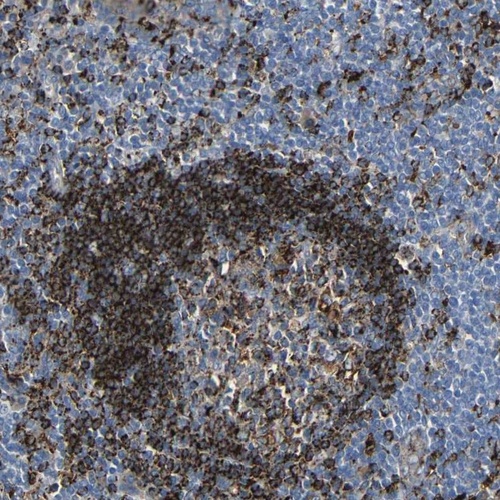

Immunohistochemistry analysis in human tonsil and cerebral cortex tissues using Anti-HLA-DMA antibody. Corresponding HLA-DMA RNA-seq data are presented for the same tissues.